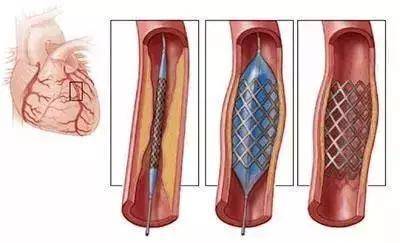

心臟支架手術,簡單來說就通過穿刺血管,讓導管順著血管一路前行。

在導管到達病灶後,再用特殊的傳送裝置將支架輸送到位。

其實相比需要開胸的心臟搭橋手術,很多情況下,支架手術有更強的普適性。

術後24小時能下床,3天即出院,這都是搭橋手術不可能達到的優勢。

每年,心臟支架手術更是拯救了數不清的患者。

心臟支架手術過程